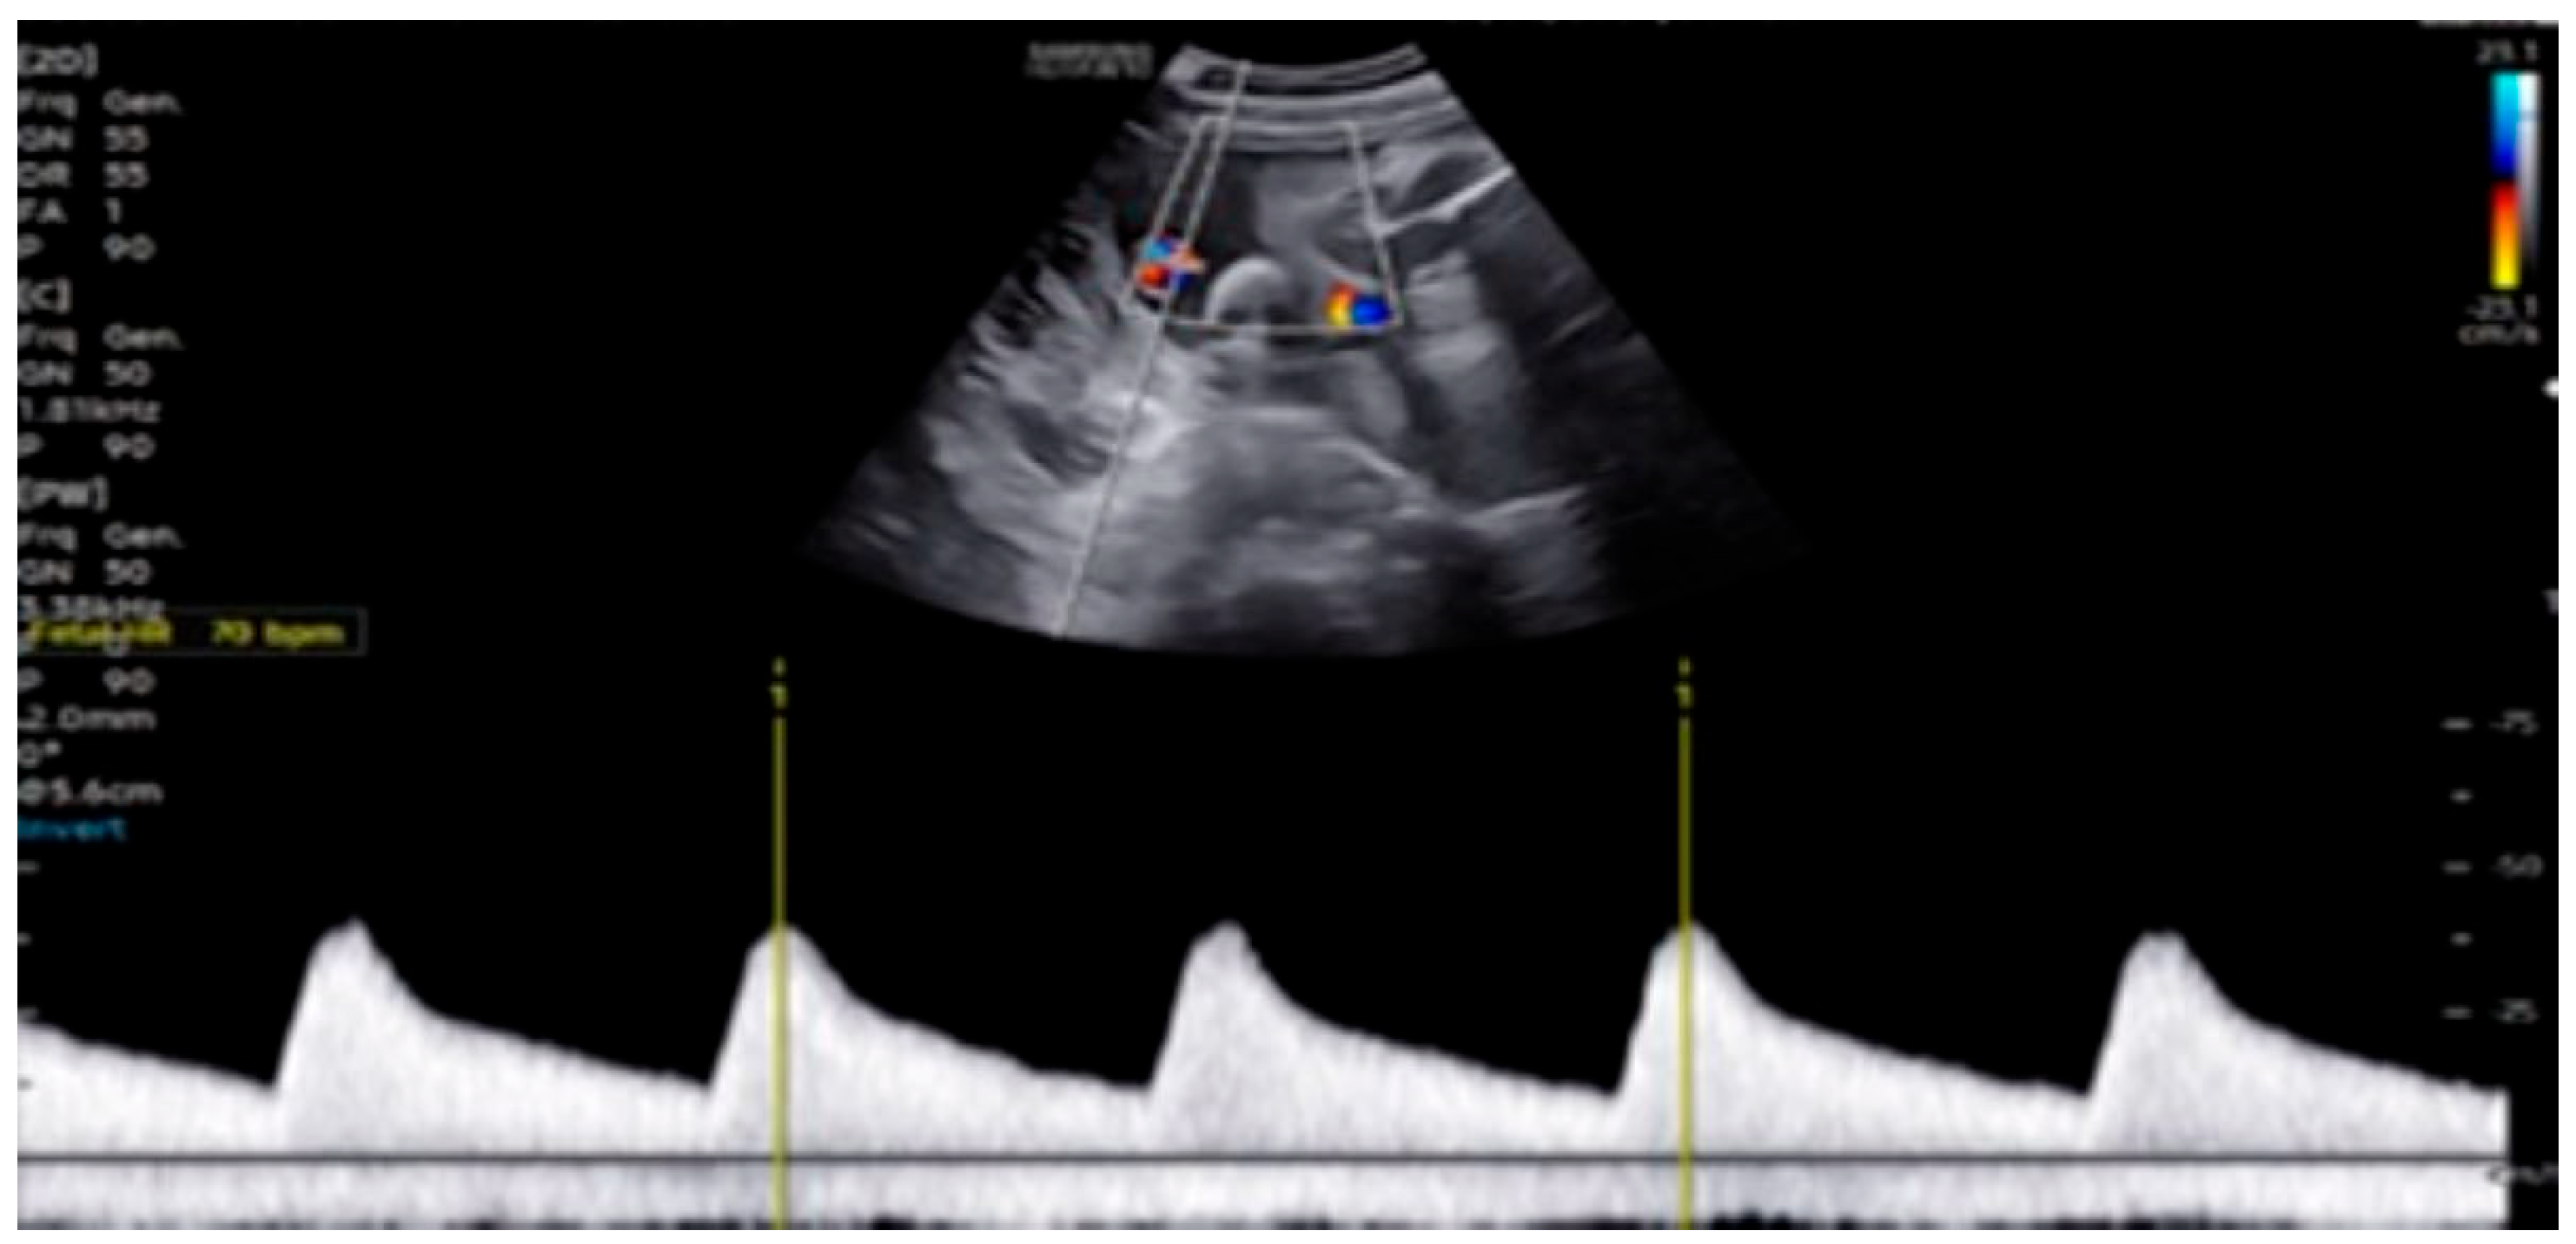

| 28 + 0 | First IVIG cycle (65 g total) | 75 | SF increased to 52%; mild improvement in contractility | Initiated due to signs of fibroelastosis |

| 31 + 2 | Post-IVIG peak response | 70 | SF: 59% (LV), 52% (RV); marked biventricular improvement | Aortic isthmus 3 mm (Z-score –1.65) |